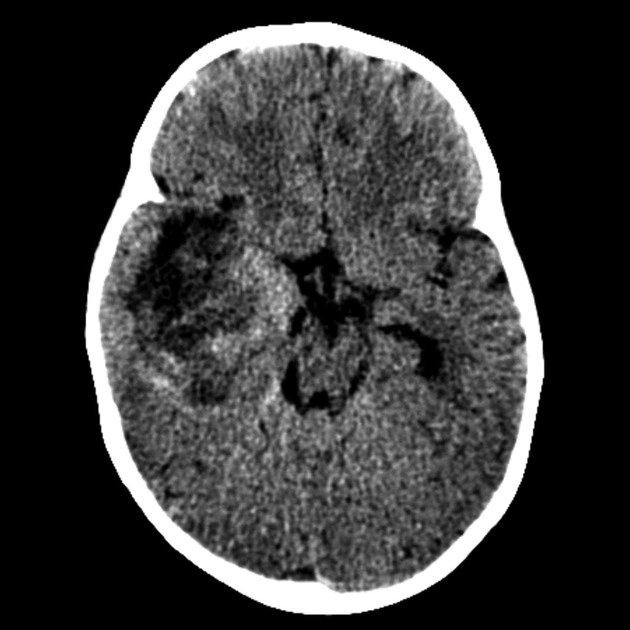

• U phôi và U nguyên bào thần kinh (Embryonal and Neuroblastic Tumors)

• U phôi sắp xếp kiểu hoa hồng (Embryonal tumor with multilayered rosettes - ETMR)

• U quái/u cơ vân dạng không điển hình (Atypical teratoid/rhabdoid tumor - AT/RT)

• U nguyên bào thần kinh di căn (Metastatic Neuroblastoma)

• U nguyên tủy bào (Medulloblastoma)